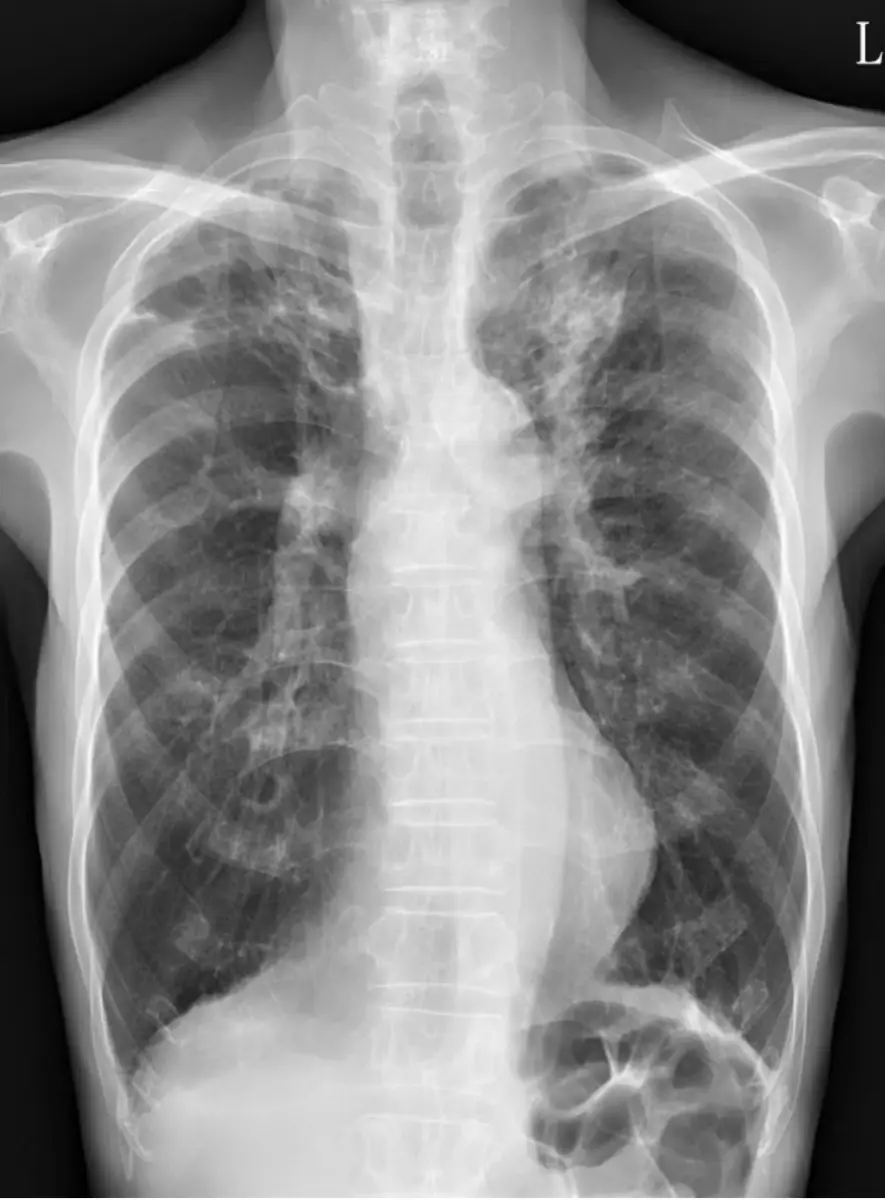

胸部 X 光可見

• 雙側肺野呈 COPD 典型的過度充氣表現:肋間隙增寬、隔肌平坦、氣管可能輕度擴張、胸廓呈桶狀。

• 右下肺野可見局灶性浸潤影(patchy consolidation),與臨床上三天黃濃痰、發燒相符,提示合併肺炎。無明顯胸腔積液或氣胸徵象。

這些影像顯示黃先生為 COPD 基底上再併發社區型肺炎(CAP),需要進一步微生物學檢測與適當經驗性抗生素治療。